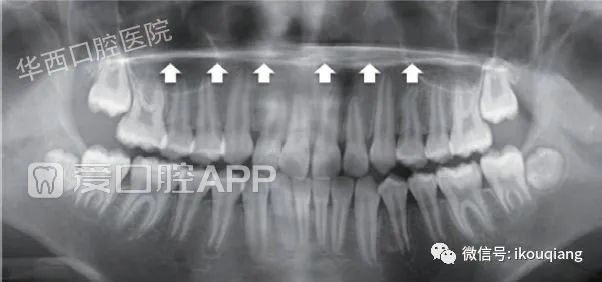

图5的曲面断层片是一位29岁的男性患者,仔细对比左右下颌后牙区可以发现,患者45、46及47近中根尖有变尖的迹象,类似于刚刚提到的“脱靴样”牙根吸收,数日后,患者确诊为白血病。所以,在临床工作中有些细节是我们绝对不能忽略的。

160000nwreaaxo9astwy9r.jpeg

▲图5 白血病患者右下颌45、46、47根尖变尖、变细,硬骨板消失